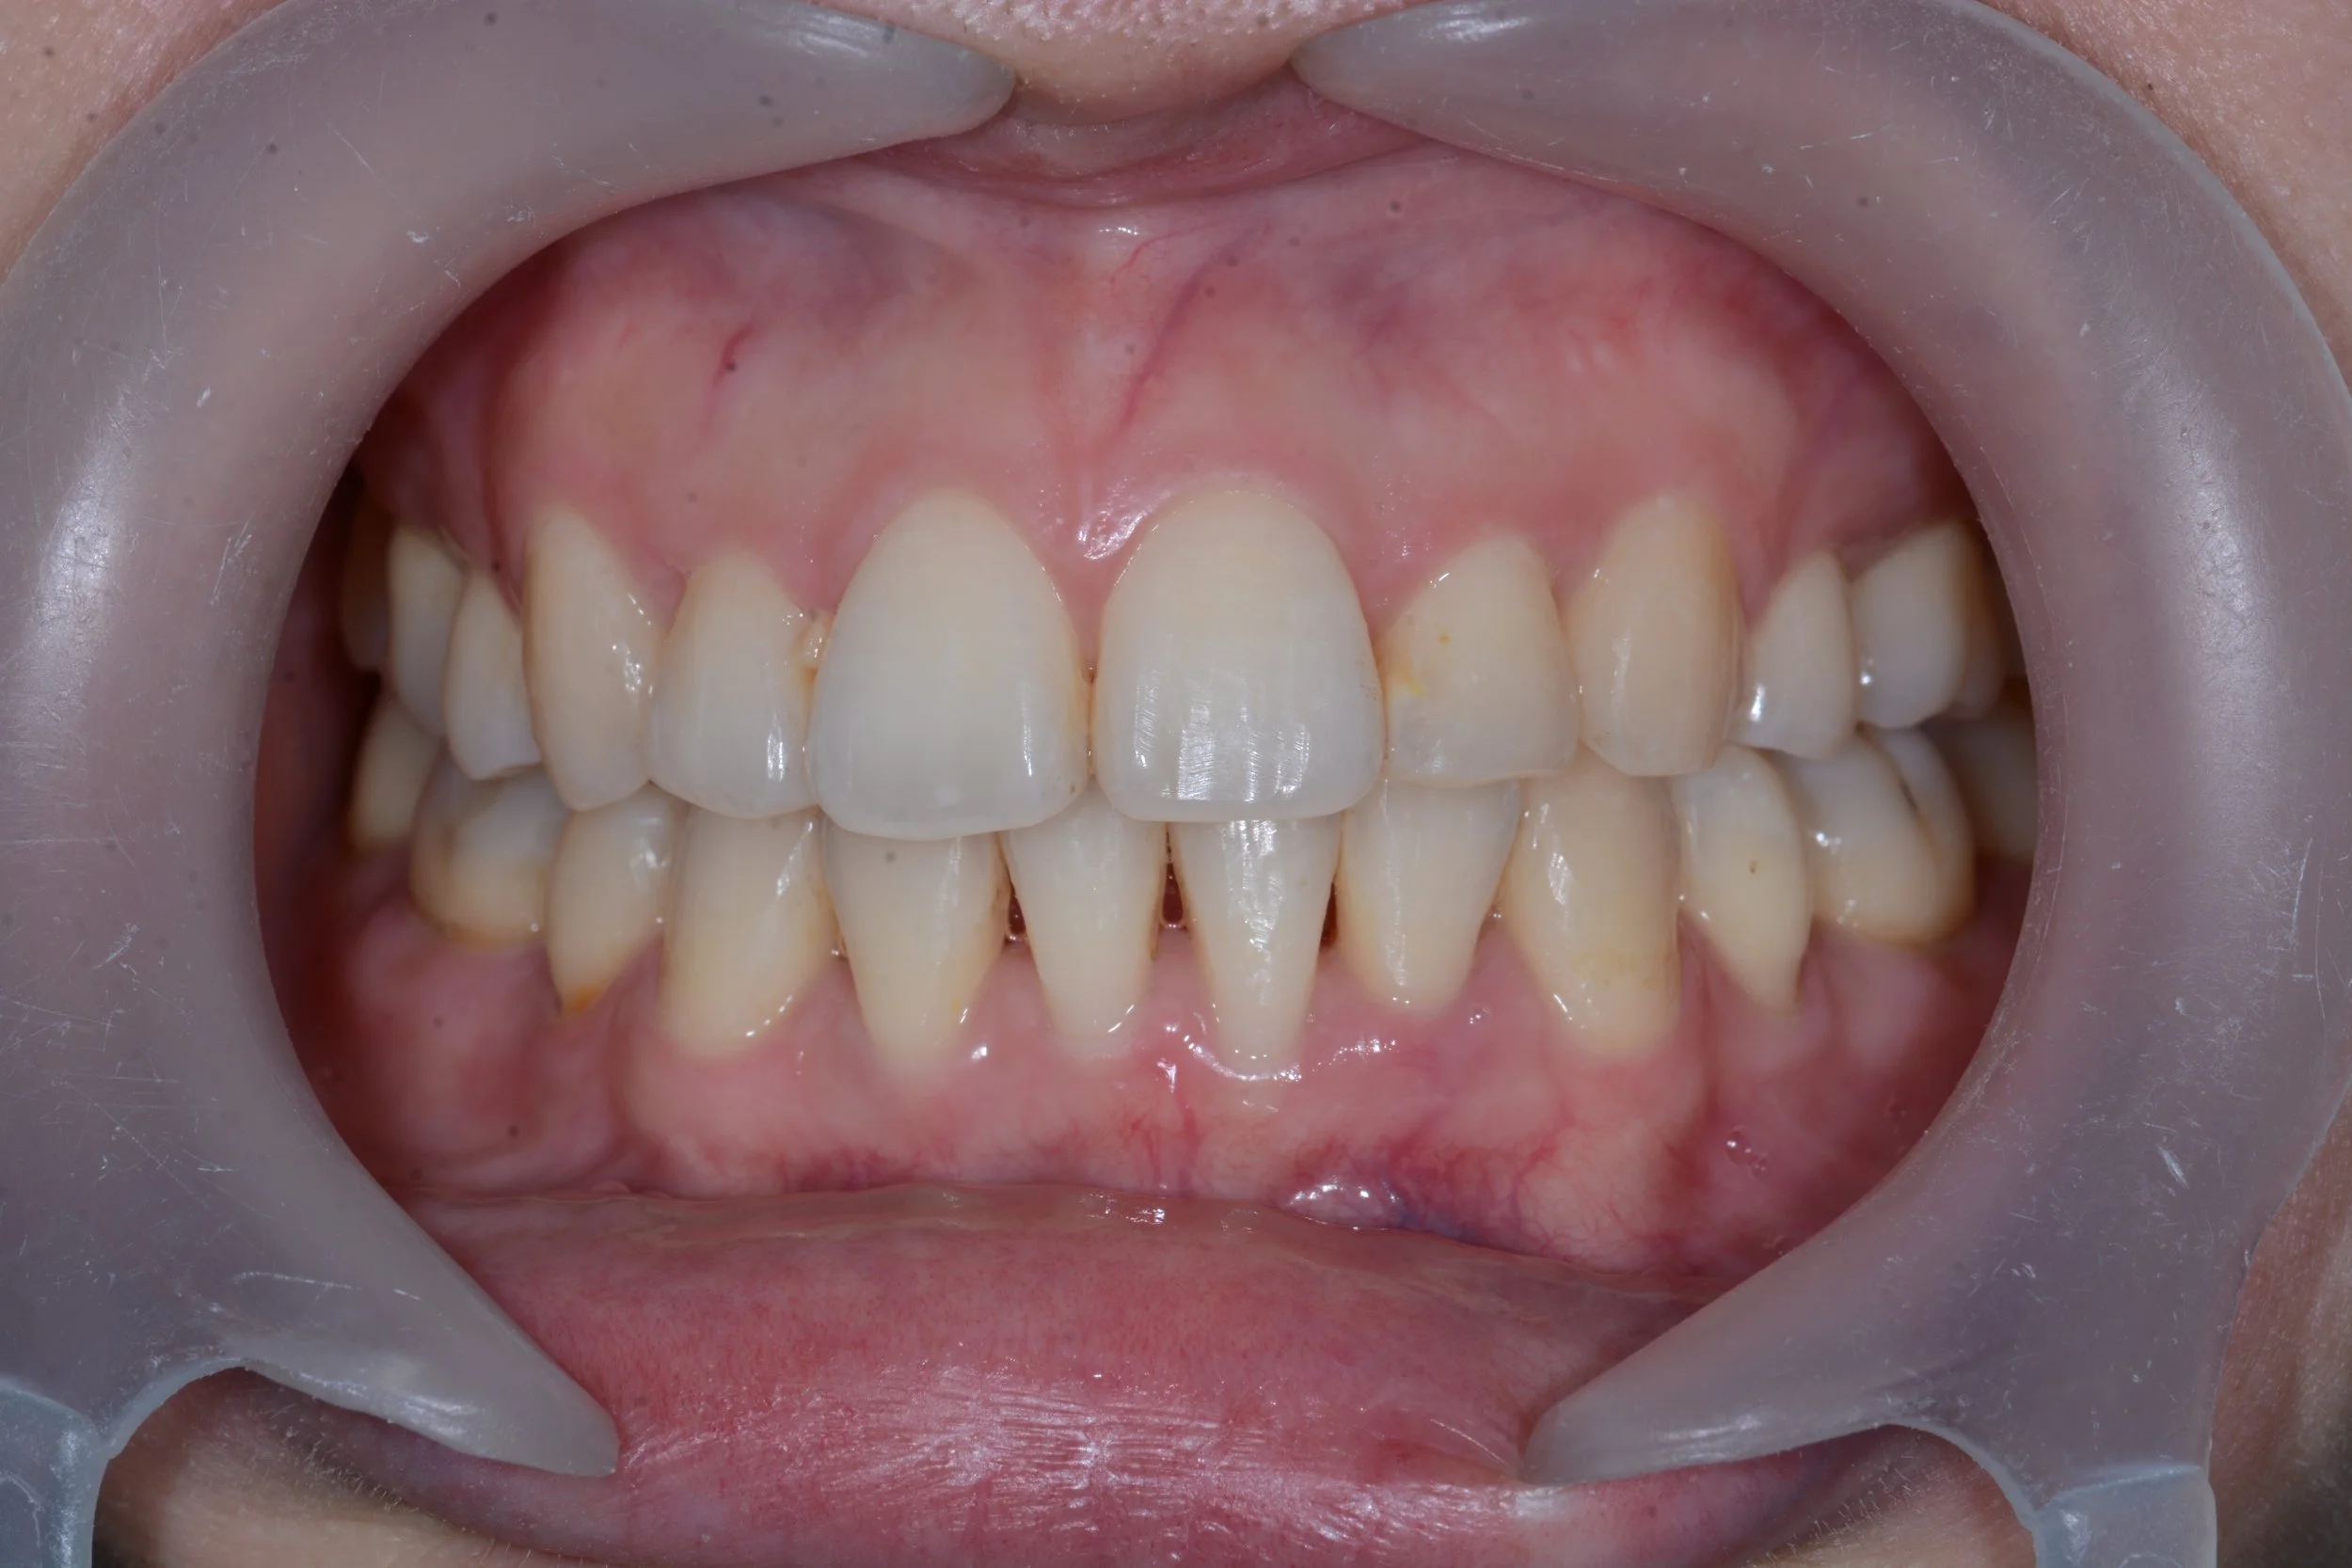

Jason Ho Issue implant-crown.jpg

Replacement with a dental implant and full ceramic crown